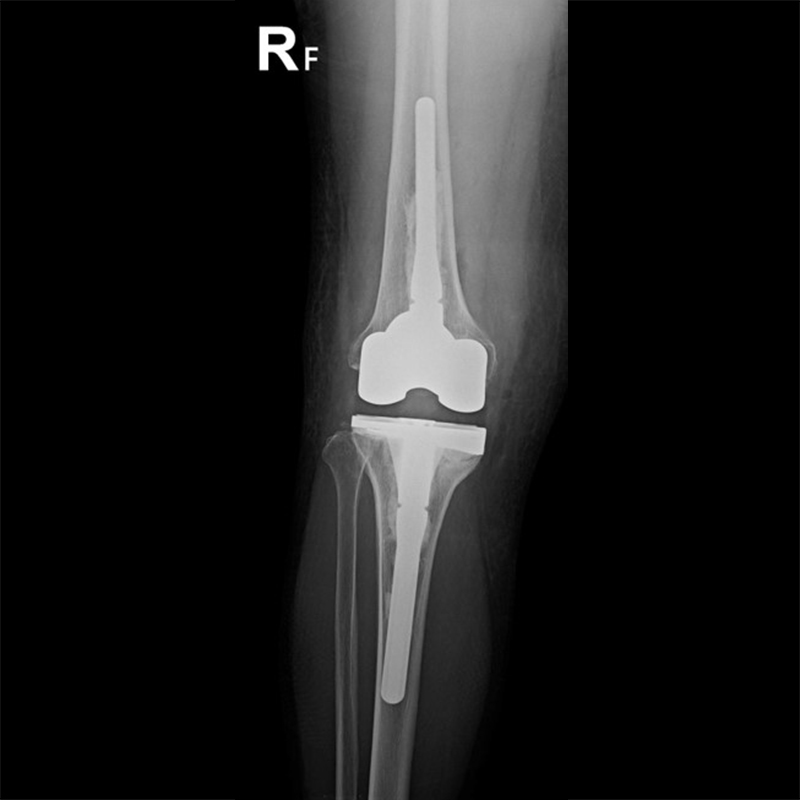

外院失敗本院再置換 首頁 案例分享 膝關節手術 外院失敗本院再置換 蕭女士 69歲 術前 術後 81歲 林女士 術前 術後 蕭女士 69歲 術前 術後 鄒女士 69歲 術前 術後 李女士 74歲 術前 術後 吳女士 71歲 術前 術後 謝女士 65歲 術前 術後